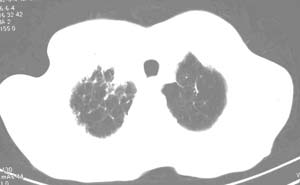

右肺上叶见片状 网格状及索条致密影.其内参杂斑点状小结节,部分融合,密度不均匀,内见含气支气管像,纵隔内见肿大淋巴结,其他肺呈代偿性肺气肿像.结合男 64  咳血,咳痰 发热 3天 血象1.2万,综合考虑:1 慢性炎症伴间质纤维化 肺气肿.2 不除外特发性感染的可能.

右肺上叶大片片状、网格状及索条致密影,前半部密实向后逐渐疏松,其内参杂斑点状小结节,密度不均匀,内见含气支气管像,纵隔内见肿大淋巴结,其他肺呈弥漫性小叶中心性性肺气肿改变,结合男 64  咳血,咳痰,发热3天,血象1.2万。考虑:1 慢性支气管炎、肺气肿合并右上肺感染。2 不除外结核合并感染的可能。

右肺上叶见片状 网格状及索条致密影.其内参杂斑点状小结节,部分融合,密度不均匀,内见含气支气管像,前段有一小片结影,纵隔内见肿大淋巴结,右侧胸腔少量积液。.结合男 64  咳血,咳痰 发热 3天 血象1.2万,综合考虑:2 右上肺感染伴间质纤维化 2 警惕细支气管肺泡癌。3建议结合临床及进一步检查[痰及纤支镜]或治疗后复查

右侧胸廓略小于左侧,右肺上叶大片实变影,近肺门处密度较高,内见支气管气相,周围较淡,呈网格状,余肺野清晰,纵隔内见肿大淋巴结,右侧胸腔少量积液。临床 咳血,咳痰 发热 , 血象1.2万。

考虑大叶性肺炎。

右侧胸阔塌陷,纵隔右移。右上肺大片状高密度影,沿支气管血管束走行,内见点状钙化;支气管充气征阳性,支气管呈柱状扩张;胸膜下小叶间隔增厚;右侧后胸壁内侧见带状水样密度影;纵隔淋巴结增大。

影像学表现:右肺上叶大片状、网格状及索条致密影,前半部密实向后逐渐疏松,其内参杂斑点状小结节,密度不均匀,内见含气支气管像,纵隔内见肿大淋巴结.